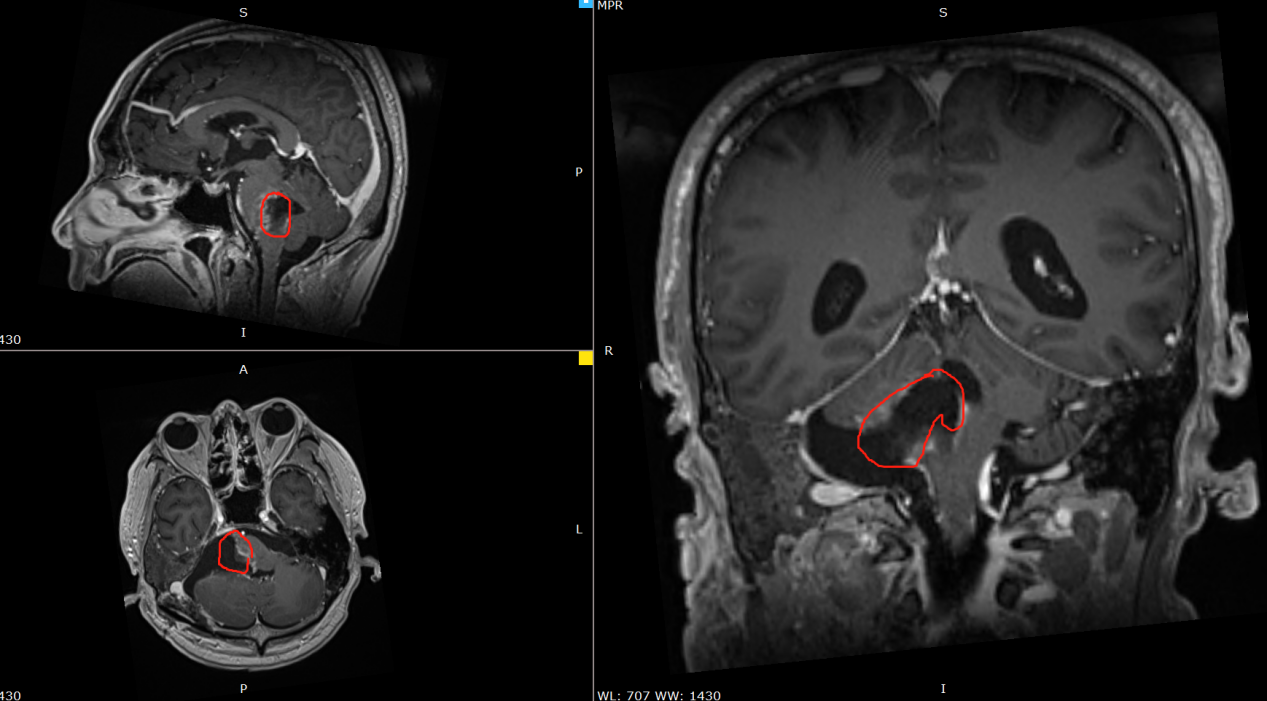

术前影像:右侧脑桥占位,与周围结构分界不清,脑干受压变薄,向左前移位。

术后影像:肿瘤占位被大部分切除,切除率95%以上。残余部分与脑干关系密切。